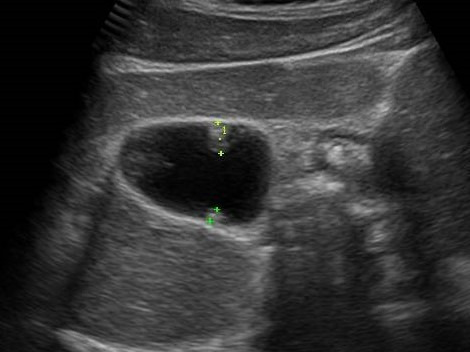

- 신장결석: 콩팥 내 결석 확인 가능

- 수신증: 요관 폐쇄 등으로 신장이 부어 있는 상태 확인

- 신장 종양, 낭종: 악성·양성 종양 여부 1차 판별